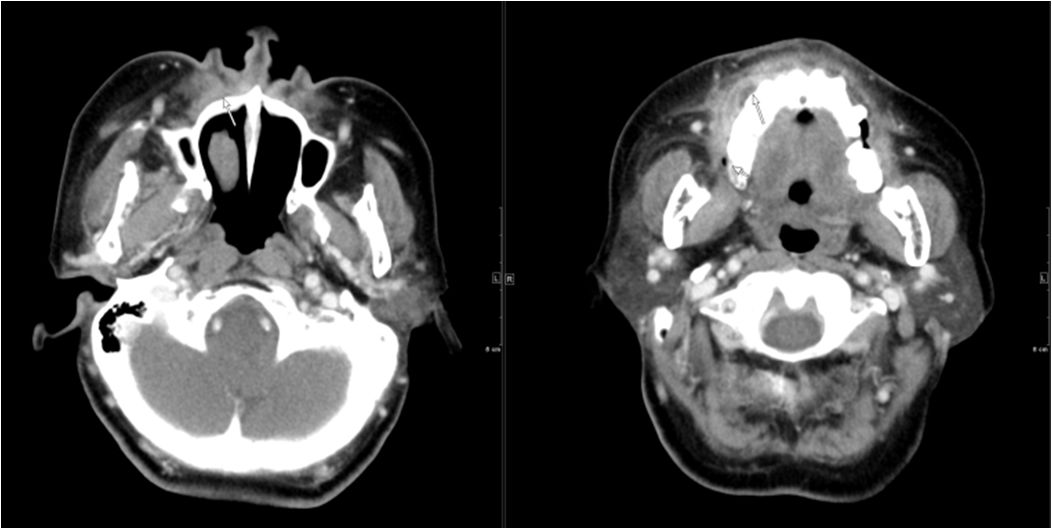

02 咀嚼肌间隙、翼下颌间隙、颊间隙

男,31岁,患者约3天前出现右侧面部口角区局限性肿胀,无明显触压痛,既往右侧下颌后牙区阵发性锐痛,曾自行口服消炎药处理,自诉牙痛症状无明显缓解,约3天前牙痛症状加重,伴夜间痛,后自觉右侧面部肿胀,约2天前开始发热,体温39.8℃。